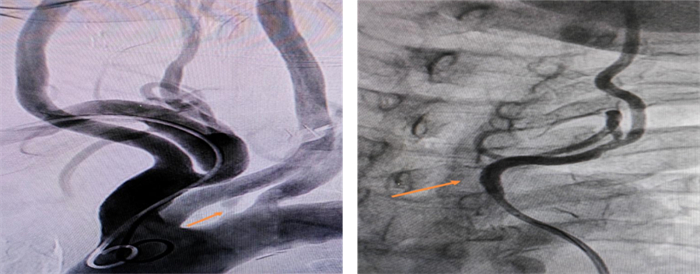

患者卓玛(化名),女,64岁, 因反复头晕来我院就诊。弓上血管CT增强诊断:1.头臂干粥样硬化,管腔局部轻度狭窄;2.右侧颈总动脉远段粥样硬化,管腔轻度狭窄;3.左颈总动脉远端少许附壁血栓形成;双侧颈内动脉C4-C6段钙化斑块,管腔轻度-中度狭窄,右侧为著;4.右侧大脑中动脉较左侧纤细,未见局限性狭窄;5.右优势型椎动脉;6.左侧椎动脉起始部非钙化斑块,管腔中度-重度狭窄;7.右侧大脑前动脉A1段较对侧纤细,考虑先天变异。行弓上血管造影提示:左侧椎动脉开口重度狭窄(狭窄90%)。

手术前(左):左侧椎动脉开口重度狭窄

手术后(右):左侧椎动脉开口支架植入后狭窄解除

整个术程迅速且顺利,术后造影证实支架位置良好,打开完全,狭窄解除,血流通畅。术后第二日患者诉头晕明显改善,未诉特殊不适,正常下床活动。患者及家属向心血管内科医护团队由衷地表示感谢。